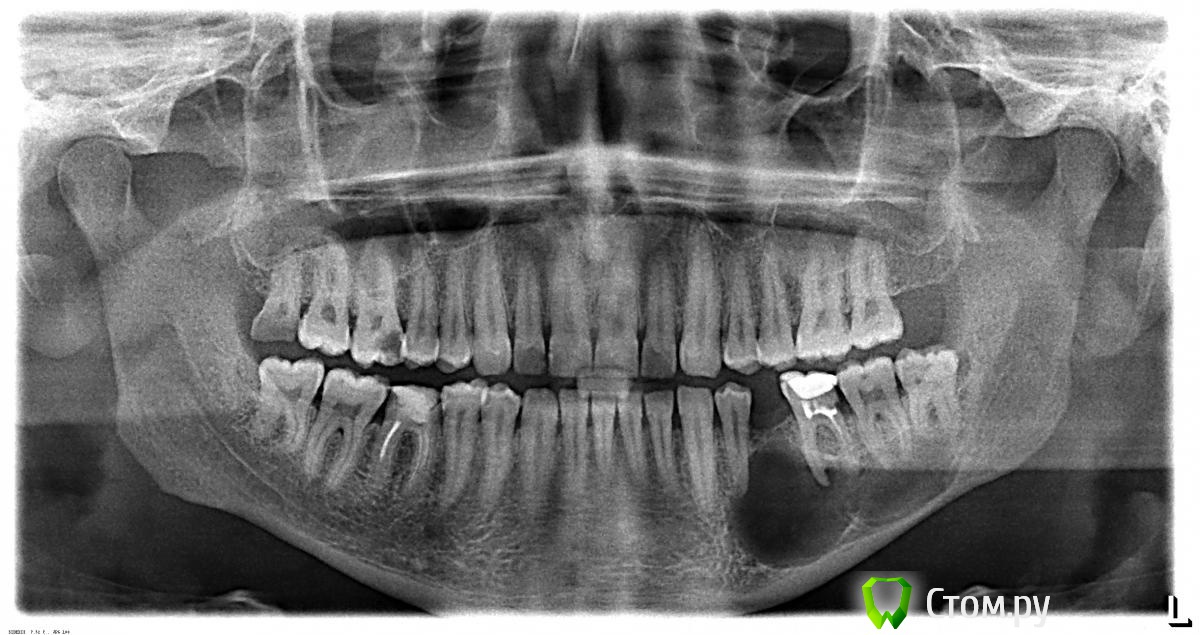

Solarys2001 Опубликовано 11 марта, 2014 Поделиться Опубликовано 11 марта, 2014 Здравствуйте. В скрепке - снимок моего мужа. Обнаружили вот такую большую кисту(Ему только 30 лет + абсолютная стоматофобия. Возможно ли в такой ситуации хотя бы частичное сохранение зубов над кистой? Вообще, в панике. Очень нужен совет! Спасибо. Ссылка на комментарий

Bier Опубликовано 12 марта, 2014 Поделиться Опубликовано 12 марта, 2014 Я бы не торопился все удалять. Проверить интактные зубы на витальность и выполнить эндодонтическое лечение 36з и тех зубов, которые не окажутся живыми. Потом ждать и наблюдать. Если не будет положительной динамики - удалени 36 зуба и цистотомия. Все можно под седацией делать. 2 Ссылка на комментарий

SergioS Опубликовано 12 марта, 2014 Поделиться Опубликовано 12 марта, 2014 (изменено) Я бы не торопился все удалять. Проверить интактные зубы на витальность и выполнить эндодонтическое лечение 36з и тех зубов, которые не окажутся живыми. Потом ждать и наблюдать. Если не будет положительной динамики - удалени 36 зуба и цистотомия.Все можно под седацией делать.Там 36 с дистальной стороны под кость разрушен, феррула нет и в помине. Скорее всего это ещё и советский резорцин.Может 37? Его на витальность ещё можно проверить и попробовать спасти,38 смысла не вижу сохранять Изменено 12 марта, 2014 пользователем SergioS Ссылка на комментарий

Zlata-doctor Опубликовано 12 марта, 2014 Поделиться Опубликовано 12 марта, 2014 (изменено) Рекомендую обязательно сделать компьютерную томографию для уточнения локализации, границ и соотношения кисты к другим анатомическим образованиям. Мое мнение. 36-скорее всего на удаление 37-пока оставить, проверить на витальность ( проверить также после операции через месяц где-то) 34-проверить на витальность 38-скорее всего на удаление. Еще момент,Solarys2001. Мы тут все видим только двухмерный снимок и выносим мнение только по представленным данным (по снимку). Есть еще масса нюансов, влияющая на постановку диагноза и соответственно на план лечения. Solarys2001, знаете ли вы о наличии у данного пациента еще множества проблемных зубов? На них тоже стоит обратить внимание...... 18,16,15,14,12,11,21,22,46,45,44-все это надо повнимательней посмотреть, от стоматофобии придется усилием воли или медикаментозно избавиться. Изменено 12 марта, 2014 пользователем Zlata-doctor Ссылка на комментарий